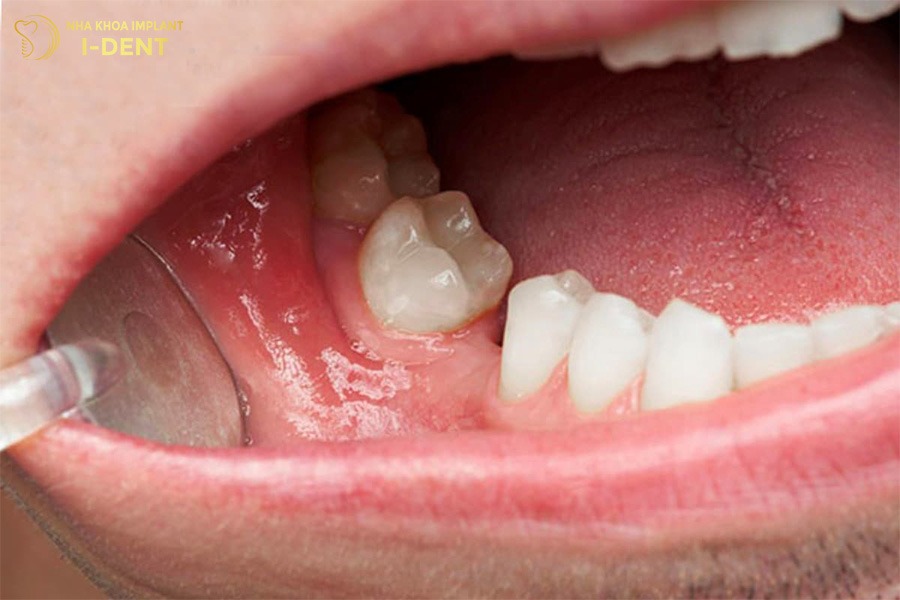

3.1. Làm yếu các răng bên cạnh

Mất răng số 6 lâu năm làm cho lực nhai bị dồn sang các răng kế cận như răng số 5 và răng số 7 khiến chúng hoạt động quá tải. Lâu dần các răng này sẽ yếu đi, lung lay hoặc dễ bị nứt gãy.

Mất răng số 6 lâu năm làm yếu các răng bên cạnh.